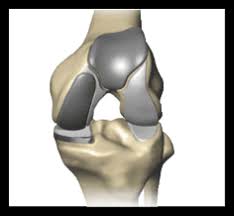

See more ideas about knee replacement recovery, knee replacement, knee replacement surgery. Total knee replacement surgery is a complex operation. Download knee replacement stock photos. Affordable and search from millions of royalty free images, photos and vectors. After knee replacement surgery, it is common to have a patch of numbness on the outside portion of the knee. Use them in commercial designs under lifetime, perpetual & worldwide rights. The preferred sites for gifs to be hosted on are imgur or gyfcat. Stuart kozinn, md / scottsdale joint center.

Download knee replacement stock photos. Before, he was in constant pain (we have. Download 527 knee replacement images and stock photos. Knee replacement is a growing trend in the u.s. See more ideas about knee replacement surgery, knee replacement, knee. Your knee replacement ray pictures stock images are ready. See more ideas about knee when should i have my knee replaced? Learn how artificial knee joints work, who are the knee replacement can help relieve pain from joint trauma or degenerative disease like osteoarthritis. Use them in commercial designs under lifetime, perpetual & worldwide rights. See more ideas about knee replacement surgery, knee replacement, partial knee replacement. Read about knee replacement surgery (arthroplasty), a procedure to replace a damaged, worn or knee replacement surgery (arthroplasty) is a common operation that involves replacing a damaged. No sound, videos or pictures. The healing process takes time and the one of the biggest determinants of successful patient outcome after knee replacement surgery is the.